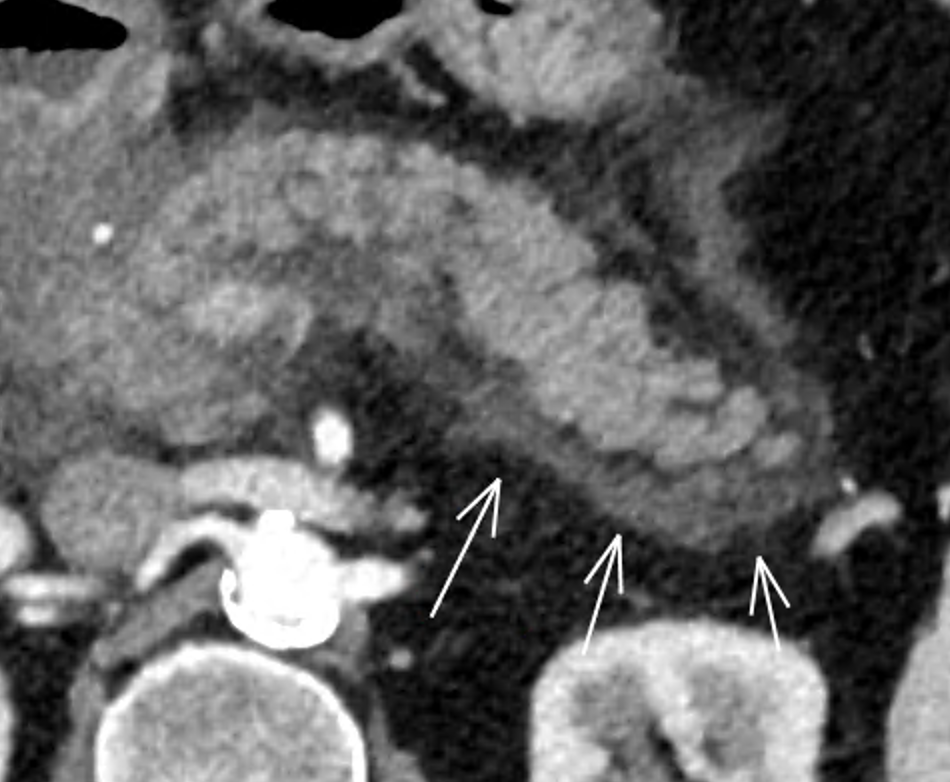

Collections

- Le CT est mauvais pour distinguer les collections liquidiennes de celles avec des débris

- Delai pour le staging: 48h

- Delai pour parler de pseudokystes: 4semaines

- Dans la pancreatite oedemato-interstitielle le liquide est limité autour du pancréas, et la complication en pseudokyte (vrai) est rare, et s’infectent très rarement

- Dans la pancreatite nécrosante, le liquide coule à distance du pancréas et fait la majorité des collections chroniques, qu’on apellait anciennement les pseudokystes mais qui sont des collections necrotiques cloisonées, qui peuvnet être steriles ou infectées